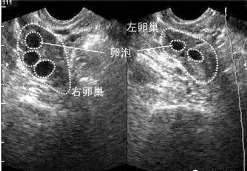

查看全文长春卵巢囊肿适合做试管吗-三代试管助孕机构 所谓试管婴儿,其实就是把卵子跟精子取出来,通过人工实验的方法将它们 […]